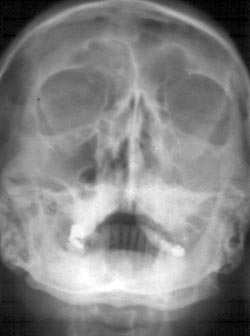

Se indicaron radiografías de tipo panorámicas y senos paranasales las cuales informaron imagen radiolúcida que abarca reborde alveolar superior izquierdo, el piso del seno maxilar correspondiente y velamiento del seno maxilar izquierdo respectivamente (Fig. 3 y 4)

Fig. 3: Imagen radiolúcida en zona postero-superior izquierda.

Fig. 4: Radiografía Water.